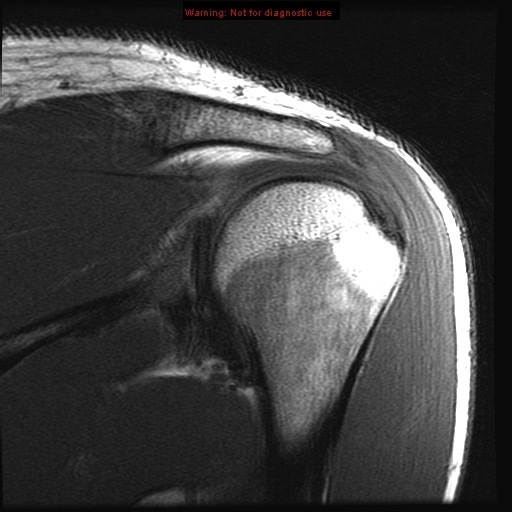

supraspinatus muscle

infraspinatus muscle

deltoid muscle

acromion

acromion acromioclavicular joint

acromioclavicular joint